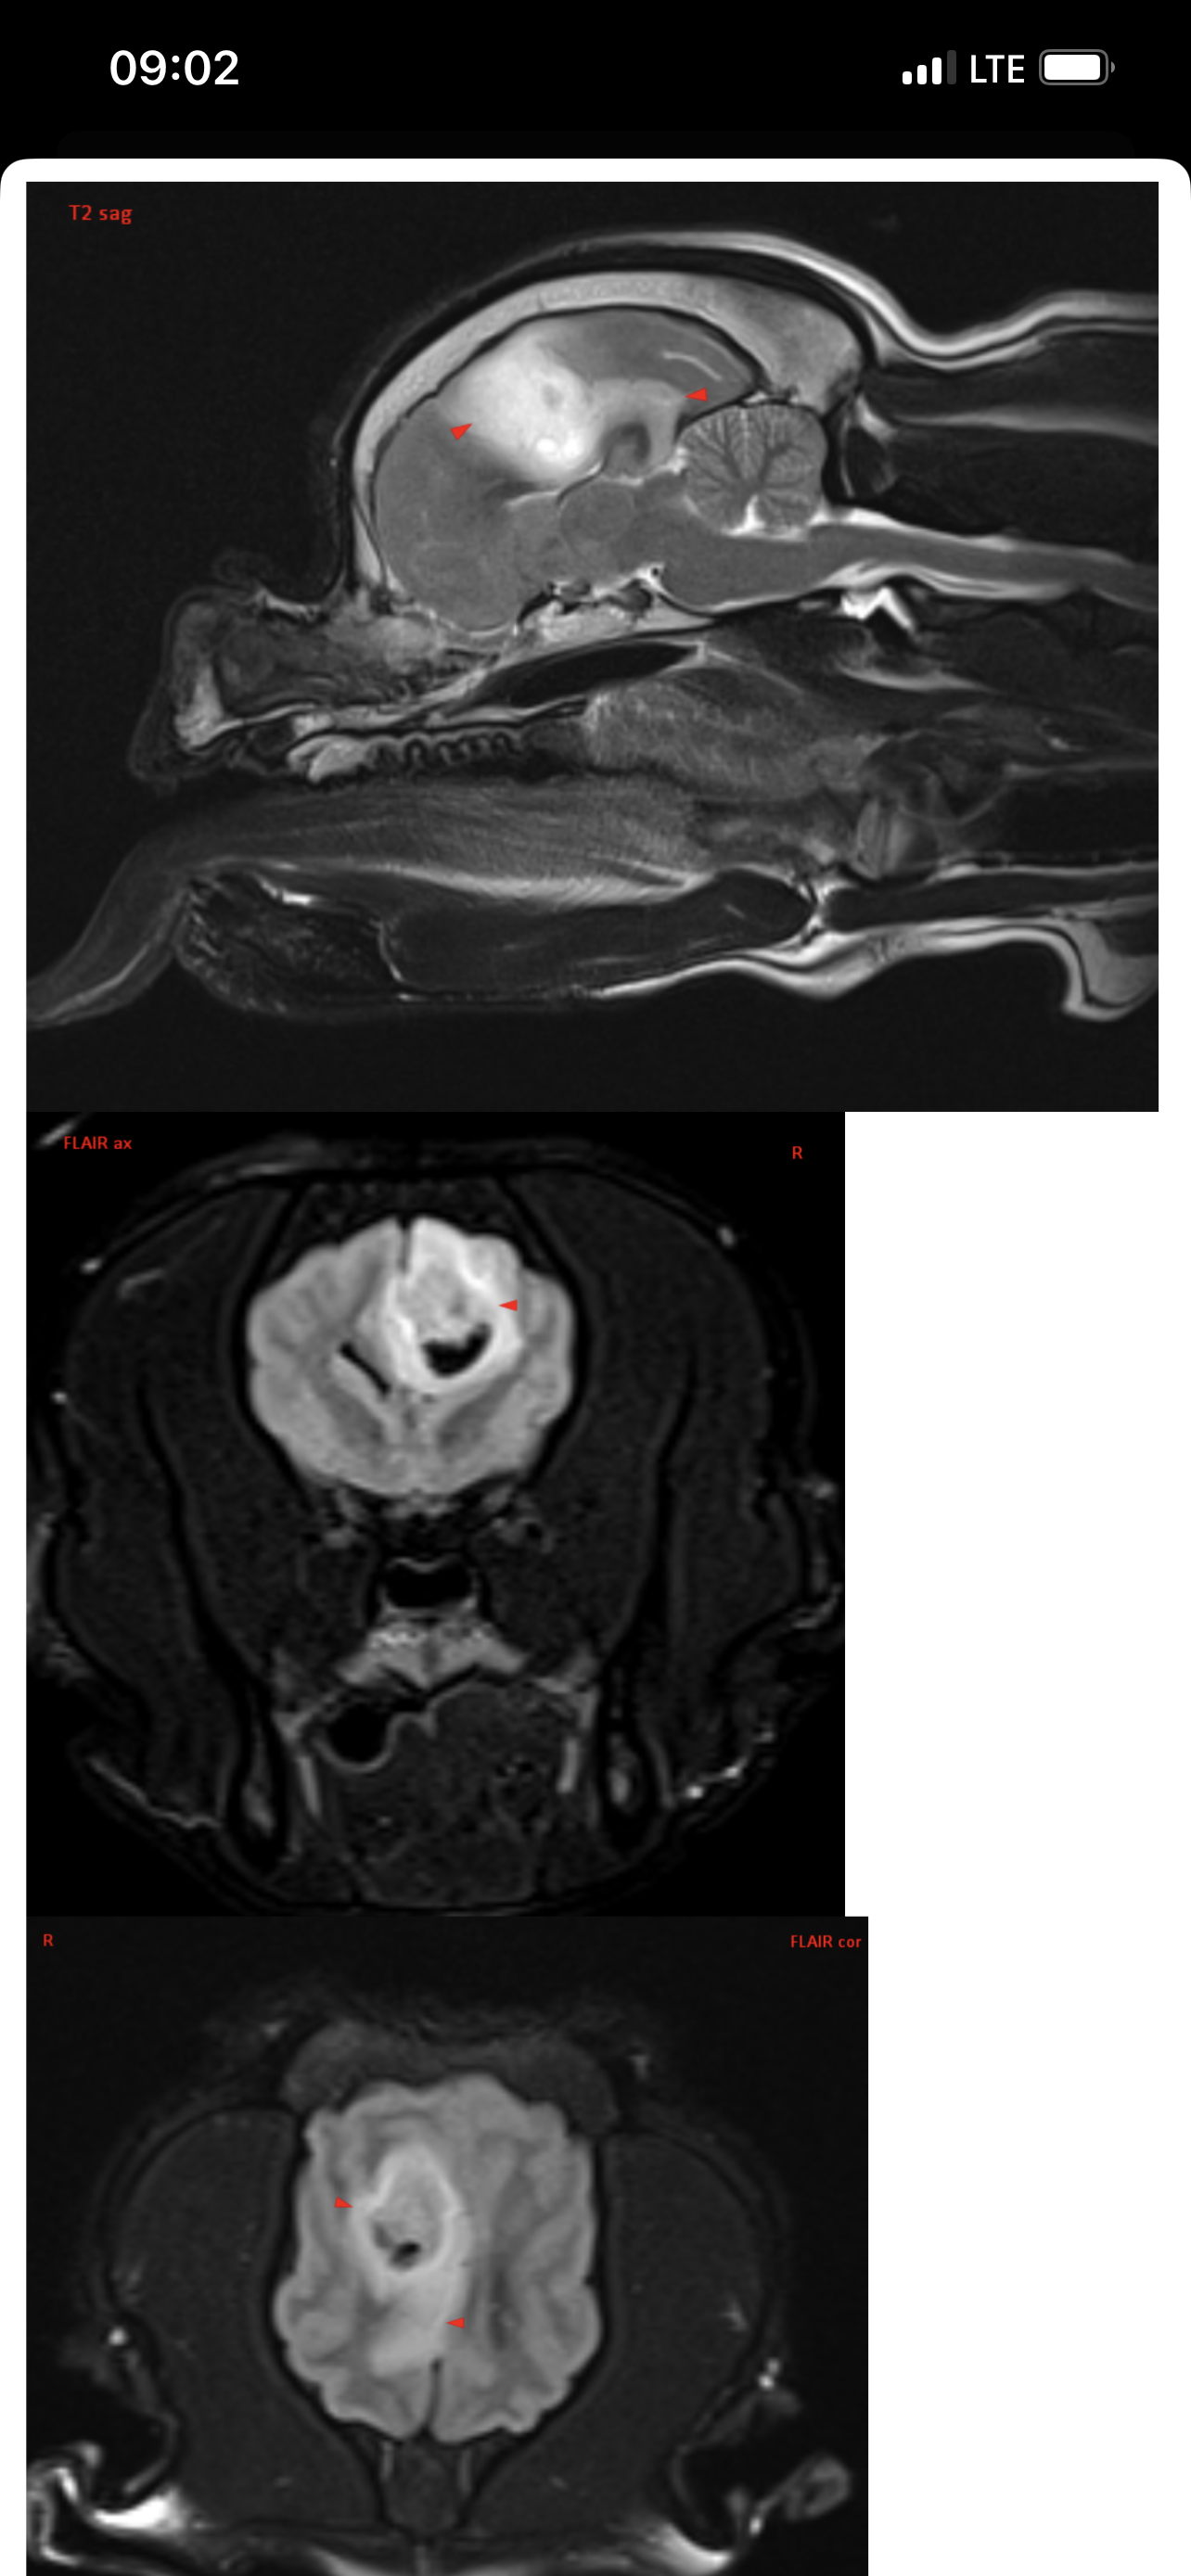

Вчера делали Марику МРТ в клинике Skolkovo Vet, если кому-то интересно, стоит чуть больше 12000₽. Результат неутешительный. Заключение:

МР-признаки новообразования в области лобной и теменной долей коры больших полушарий головного мозга справа, с очагами кровоизлияния и перифокальным отеком.

МР-признаки постсудорожных изменений.

Опухоль у моего мальчика(( она и вызывает судороги. Написала сегодня в вотс ап Хохлову, не знаю ответит ли, готова ехать к нему в клинику если он вообще принимает пациентов. К Дубовицкой попасть нереально, там очередь минимум на 1,5 месяца, есть онлайн консультация, стоит как и очный прием 7000₽, но ее рекомендуют скорее как второе мнение после очного осмотра у невролога. Рекомендовали еще Субботина из Белого Клыка, но увы, он по известным всем причинам с 2022 работает в вет клинике в Грузии. Продолжаю давать Кеппру и Габапентин

Итак, в прошлую субботу, когда въезд в Москву перегородили танки, над городом кружили вертолеты и не работала навигация, мы с Мариком были на приеме у уважаемого Алексея Валерьевича Хохлова. Он изучил снимки головного мозга, опухоль Марика он назвал скорее кистой и предположил, что живет он с ней уже давно, естественно ни о каком оперативном вмешательстве речи не идет. Спустя неделю после эпистатуса Марик почти полностью восстановился, но по лестнице сам еще не поднимается, Хохлов его состоянием доволен и никаких тревожных симптомов не обнаружил. Он прописал: Паглюферал1 - по 1/4 2 раза в день, Габапентин 300 по 1/2 2 раза в день, Кавинтон 5мг по 1/4 2 раза в день. Кеппру не прописал! Так же выдал рекомендации и список лекарств если будут приступы, что и как колоть, но эти схемы тут всем давно известны. Неделю мы принимаем все вышеизложенные препараты, пока все нормально, живем дальше с Божьей помощью!